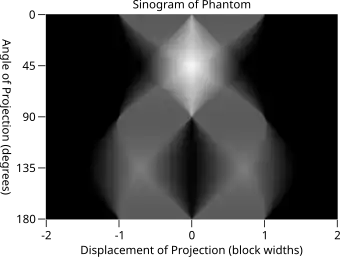

Radon transform of the indicator function of two squares shown in the image below. Lighter regions indicate larger function values. Black indicates zero.

The Radon transform data is often called a sinogram because the Radon transform of an off-center point source is a sinusoid. Consequently, the Radon transform of a number of small objects appears graphically as a number of blurred sine waves with different amplitudes and phases.

Explicit and computationally efficient inversion formulas for the Radon transform and its dual are available. The Radon transform in dimensions can be inverted by the formula:[11] where , and the power of the Laplacian is defined as a pseudo-differential operator if necessary by the Fourier transform: For computational purposes, the power of the Laplacian is commuted with the dual transform to give:[12] where is the Hilbert transform with respect to the s variable. In two dimensions, the operator appears in image processing as a ramp filter.[13] One can prove directly from the Fourier slice theorem and change of variables for integration that for a compactly supported continuous function of two variables: Thus in an image processing context the original image can be recovered from the 'sinogram' data by applying a ramp filter (in the variable) and then back-projecting. As the filtering step can be performed efficiently (for example using digital signal processing techniques) and the back projection step is simply an accumulation of values in the pixels of the image, this results in a highly efficient, and hence widely used, algorithm.